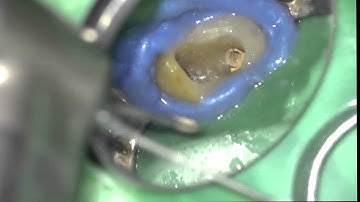

How to remove a fiber post